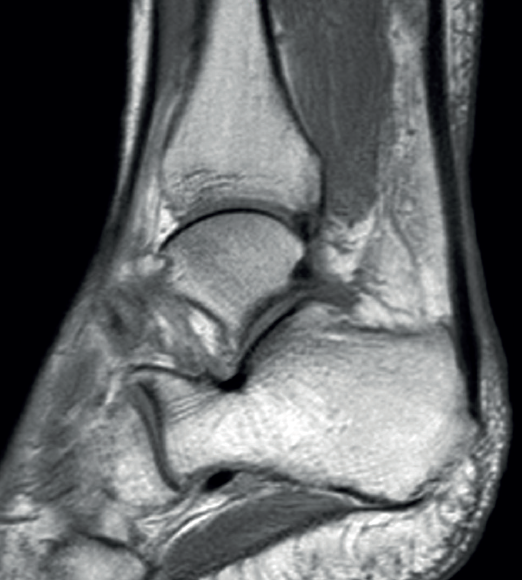

The normal Achilles tendon is observed as a hypointense structure in both T1- and T2-weighted sequences(33)(Figure 3). In the sagittal plane its margins are parallel, and in the axial plane its distal portion presents an anterior concave margin towards the calcaneus over most of its course. The thickness is similar along its trajectory, and a minimum amount of fluid is observed at retrocalcaneal level (fluid surrounding the tendon is pathological)(34).

Figure 3. Magnetic resonance imaging view of ankle (T1 sequencing). Sagittal view showing a normal tendon.